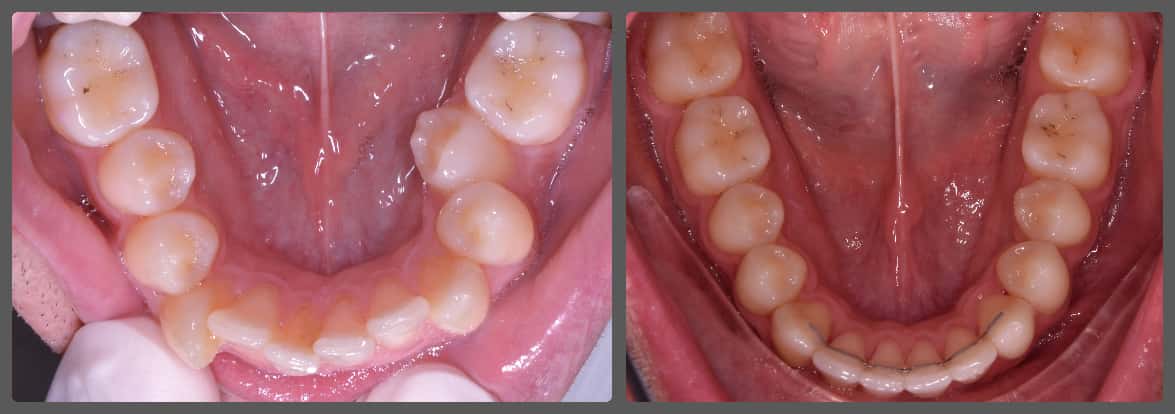

Zoli torlódott alsó fogai miatt szeretett volna fogszabályozó készüléket. Régebben 2 db felső kisőrlő fog eltávolításával már fogszabályozták, azonban az alsó fogív eltérései jelentősek voltak. A torlódás mellé közepes mértékű mélyharapás társult, valamint a bal oldali kisőrlő fogaknál non-occlusiot figyeltem meg. Ez azt jelenti, hogy esetünkben a felső első kisőrlő fog az alsó első és második kisőrlő fog közé, de azok külső felszínére harap. Ez a felső fogat kifelé, az alsókat befelé, a nyelv felé dönti és hosszútávon súlyos elváltozást okoz. Alsó-felső Pitts21 rögzített fogszabályzóval, intermaxilláris gumihúzással, harapásemelőkkel és tolórugókkal Zoli fogait nagyon gyorsan, 13 hónap alatt sikerült tökéletes pozícióba szabályoznunk, mind esztétikai, mind funkcionális szempontból (persze ehhez kellett a töretlen lelkesedése, együttműködése is). A kezelés végén az alsó fogívre fix retainert helyeztem fel az elért állapot megőrzésére. A végeredmény úgy gondolom mindent elmond!